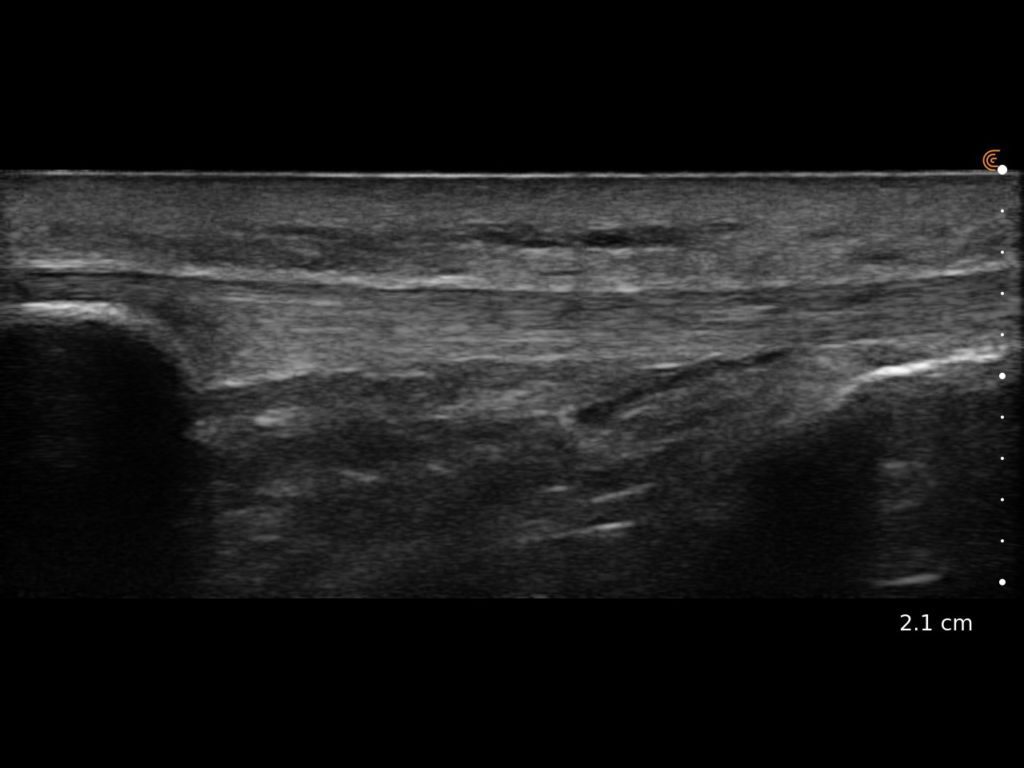

Clarius HD3 is the ideal wireless ultrasound scanner for musculoskeletal (MSK) imaging and procedural guidance. Make a confident diagnosis with high-resolution imaging of muscles, joints, ligaments, tendons, and cartilage both at rest and in motion.

What I like about Clarius is that it is an excellent ultrasound that allows me to have versatility, quality and precision.